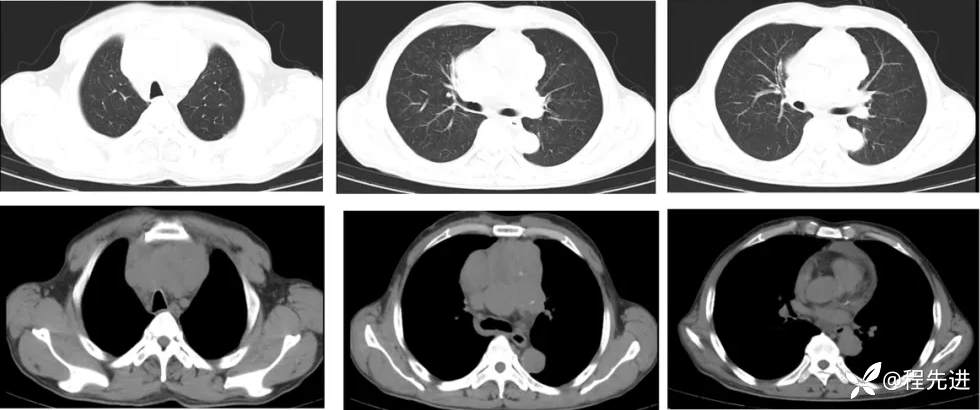

【主诉】:全身乏力近1月,发现纵隔占位20天

【现病史及既往史】:1月前因“脑梗死”就诊于外院进行治疗,住院期间行胸部CT检查提示纵隔占位

影像检查: